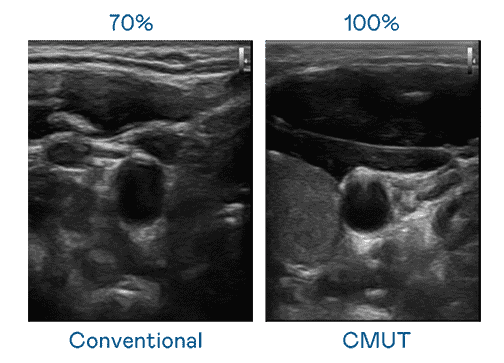

CMUT 技术是一种用电容式微机电元件来产生超音波讯号的技术。。。。与传统 PZT 压电式技术相比,,CMUT 频宽增加 30%,,,更宽频的超音波讯号让影像解析度大幅提升,,,是实现高影像品质医疗超音波扫描、、、、促进精准医疗发展的关键技术。。

超音波影像的解析度高低,,首先取决于探头能发出的讯号频宽。。。尊时凯龙 CMUT 可提供高清晰的超音波讯号,,提供高频宽、、、、高灵敏度、、影像纹理细节更高的超音波影像,,,协助医护人员缩短影像判读时间及利用精准的医疗影像进行诊断。。